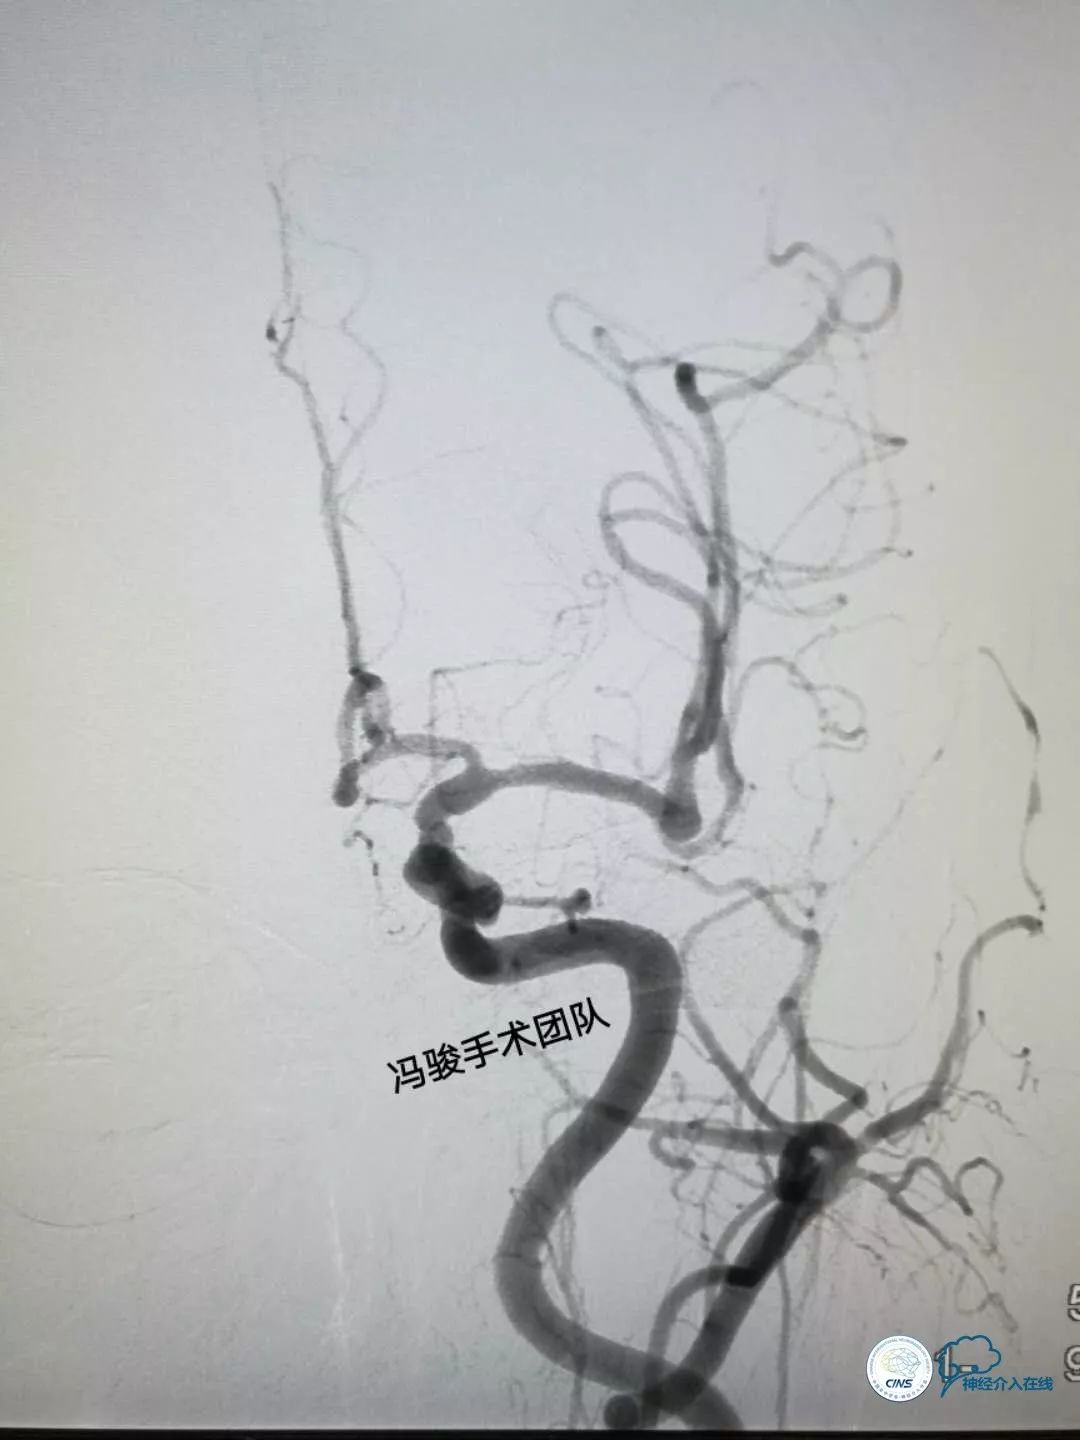

再次造影,显示左椎动脉V4段狭窄解除,双侧大脑后动脉及左PICA均血流通畅。

术后患者很快复苏,活动自如,言语流利,头晕症状消失,满意出院。